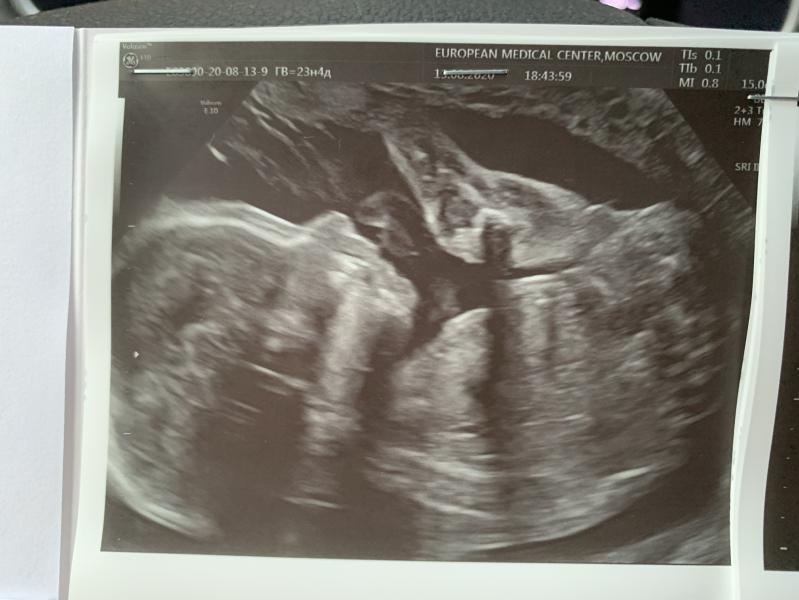

Очередные вести с полей. И поход на узи🙏🏻

Мои мальчишки отлично растут! Очень прошу их нажирать попки и щечки- справляются 😂

622 и 639 гр

Я не понимаю, как доктор вообще на узи что то понимает! Я вижу лишь месиво из конечностей😂😂 У одного уже пятки на лице 😂😂

Сфотографировать мордочки нормально не удалось , как ни крутили.

Плохая новость в том, что шейка укоротилась. Сейчас она 34, да еще не страшное значение, но есть тенденция. Скорей всего будут ставить пессарий. Если утрик и ...